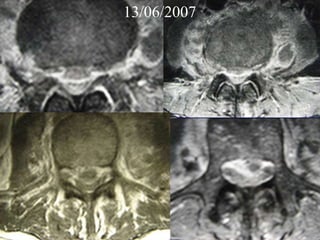

13/06/2007

04/06/2007